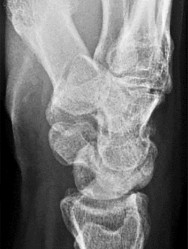

A 30-year-old male sustains an axial load to a plantarflexed foot. On physical examination, there is pronounced plantar ecchymosis and localized pain with passive pronation and abduction of the forefoot.

The primary stabilizing ligament of the disrupted joint complex connects which two osseous structures?

Explanation

Plantar ecchymosis in the midfoot is the pathognomonic sign of a Lisfranc injury. The Lisfranc ligament is an interosseous ligament that represents the strongest and most critical stabilizer of the tarsometatarsal complex. It runs obliquely from the lateral aspect of the medial cuneiform to the medial base of the second metatarsal. There is notably no direct transverse ligamentous connection between the bases of the first and second metatarsals.